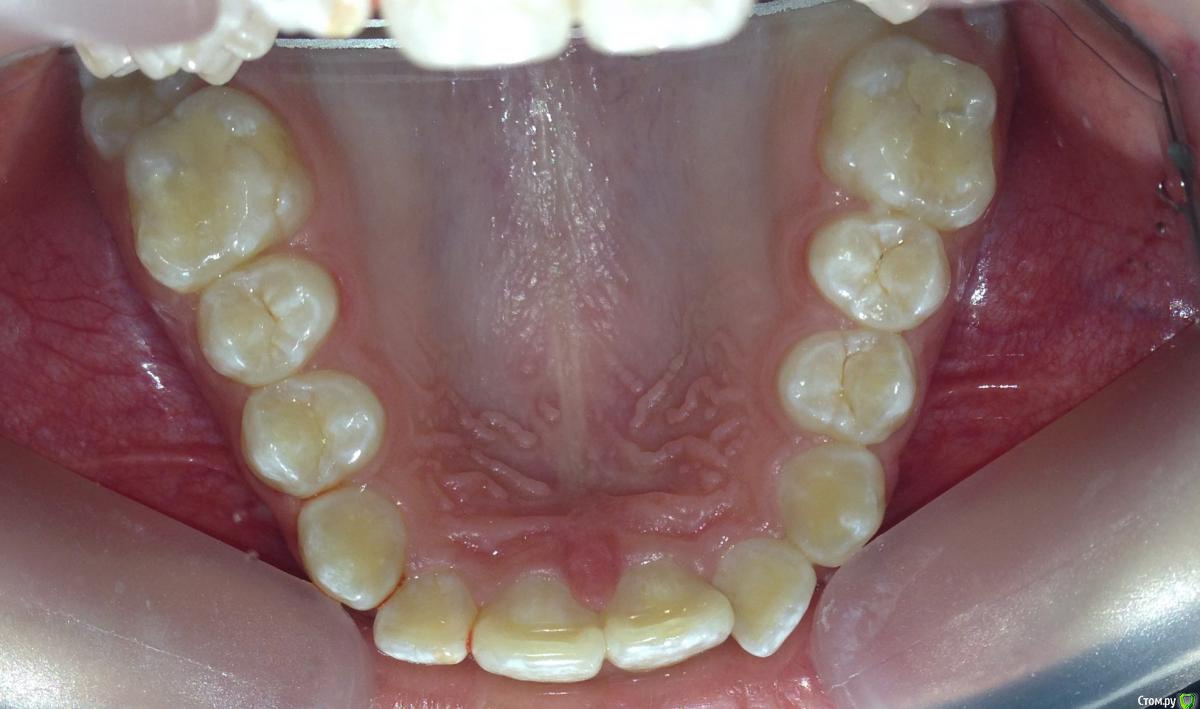

post-38874-0-87186300-1459536185_thumb.jpgpost-38874-0-15339500-1459536188_thumb.jpgpost-38874-0-82577500-1459536190_thumb.jpgpost-38874-0-61079300-1459536193_thumb.jpgpost-38874-0-22178300-1459536196_thumb.jpgpost-38874-0-56404400-1459536198_thumb.jpgpost-38874-0-43380300-1459536199_thumb.jpgpost-38874-0-04081600-1459536228_thumb.jpgpost-38874-0-34503200-1459536230_thumb.jpgpost-38874-0-34236500-1459536233_thumb.jpgpost-38874-0-95387400-1459536234_thumb.jpgpost-38874-0-86290600-1459536242_thumb.jpgpost-38874-0-47956700-1459536252_thumb.jpgpost-38874-0-98507600-1459536273_thumb.jpgpost-38874-0-52220700-1459536283_thumb.jpgpost-38874-0-12327700-1459536263_thumb.jpg

Извините за качество фото.

Пациентка 14 лет. Было принято решение лечить без удаления, тк. профиль не позволяет да и ретропозиция нч. Лечение идет. Я назначила ранние эластики слабые, на 17/25 нити на вч и 18 нити на нч. по 2 классу короткие 3,4-4,5. Пациентка пришла через месяц жалуется на щелканье челюсти во время ношения эластиков и сразу после их снятия. Т.е. если открывает рот, то челюсть скачкообразно двигается и щелчками. Последние 2 недели, когда много говорит, то вообще стала заедать. Это она так сказала. После отмены эластиков (страшно), через неделю пришла, рот открывает ровно, без девиации, щелчков нет. Вопрос: почему щелкает и что с этим делать? По поводу прикуса, посоветуйте, пожалуйста, как нормализовать? Аппарат типа гербста? может ей твинблок сделать? Эластики? К сожалению другими методами я пока что не владею. Спасибо, очень жду ваших советов.